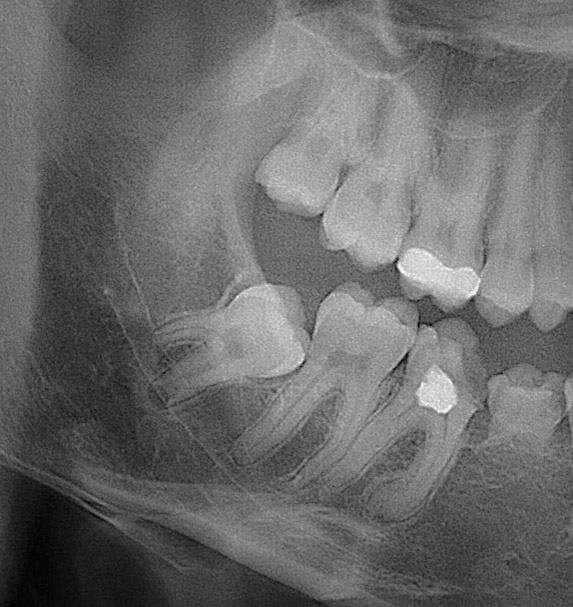

🦷 Зуби мудрості, 🎱 вісімки, часто викликають біль🤦 , запалення або тиснуть на сусідні зуби.😖 Їх видалення вимагає спеціальних навичок- і ми це вміємо. В АРТ Стоматології проводимо видалення зубів мудрості, будь якої складносі, яке можливо в амбулаторних умовах.

✅ 3Д планування та рентген диагностика

Первинний осмотр у стоматолога, рентгенологическое исследование, при наличии показаний принятие решения об удалении зуба мудрости.